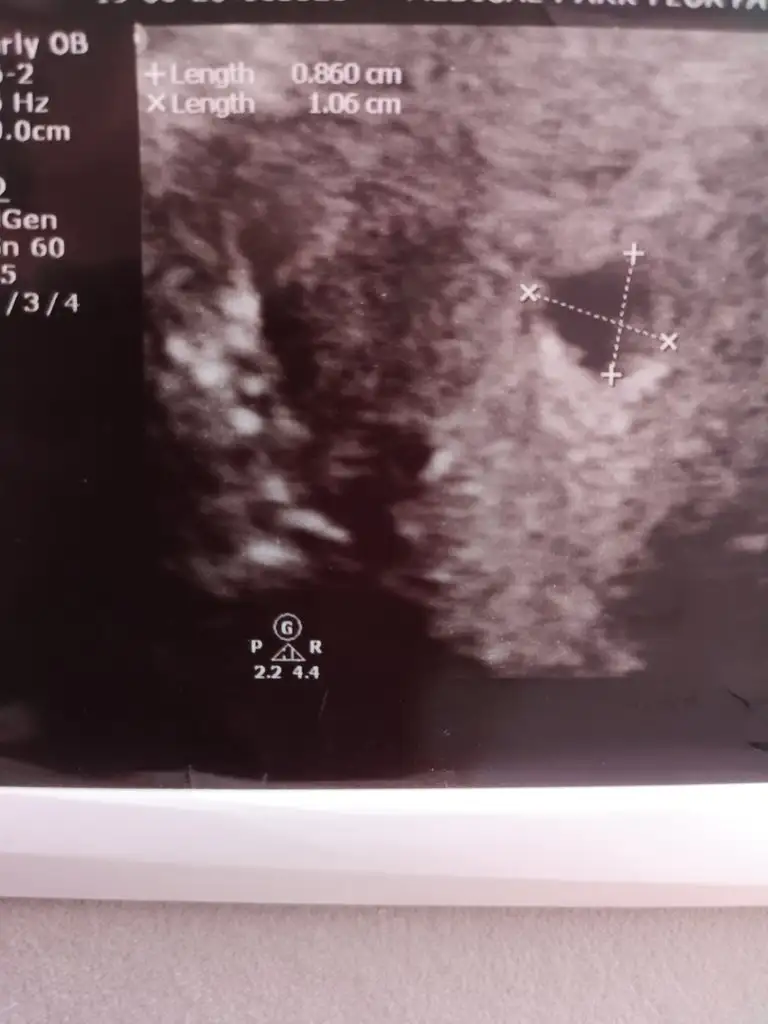

Merhaba beta hcg değerleriniz nasıl artmıştı hatırlıyormusunuz? Şu an aynı durumla karşı karşıyayım çok korkuyorum.Bende yaşadım.9. haftaya kadar bekledik beta artıyordu ama iki katı artmiyordu.Kürtaj için gün aldığım akşam düşürdüm.Beta 16000 lere çıkmıştı.Bir müddet sonra kese bozuluyor zaten.Lekelenmeler başlıyor..Kese 15 mm olup içinde hala embriyo yoksa boş gebelik diyorlar

Söylemedi onu. Bunlar var elimdeKese kaç mm

5800 den sonra iki katı artmamaya başladı.Kese büyüyordu ama bebek yoktu.Kese 20mm olmustu en son hcg 16000 lere çıkmıştı.Kürtaj dedi doktor .5.haftada kalmış kese meğer.12 haftalık olması gerekiyordu adete göre.Düşük yaptım kese bozulunca

Geç dollenme olabilir canim dr lar 9 haftaya dek bekleyebiliyor insallah her sey istediginiz gibi olur ...Merhaba son adet tarihime göre 6+5 günlük hamileyim. Geçen hafta 5+6 günlükken doktora gittiğimde kese göründü ancak embriyo görünmedi yarın bir daha gideceğim ama boş gebelik olursa diye korkuyorum geçen hafta embriyoyu göremediğim için. Acaba 5+6 haftalıkken embriyonun görünmemesi normal mi ve yarın gittiğimde görebilir miyim? Sizlerde embriyo ne zaman görünmüştü ve kalp atışı ne zaman alınmıştı? Yorumlarsanız sevinirim...